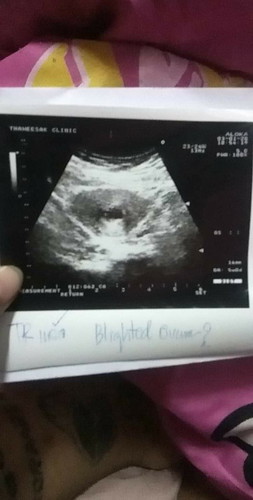

เสียใจมากอุตส่าห์ดีใจว่าจะมีตัวน้อยที่ไหนได้ท้องลม?

ใครเคยท้องลมบ้าง?

หมายถึงอะไรคะท้องลม

ท้องลมคือไม่มีเด็กค่ะ ไข่ฝ่อไปเอง😔